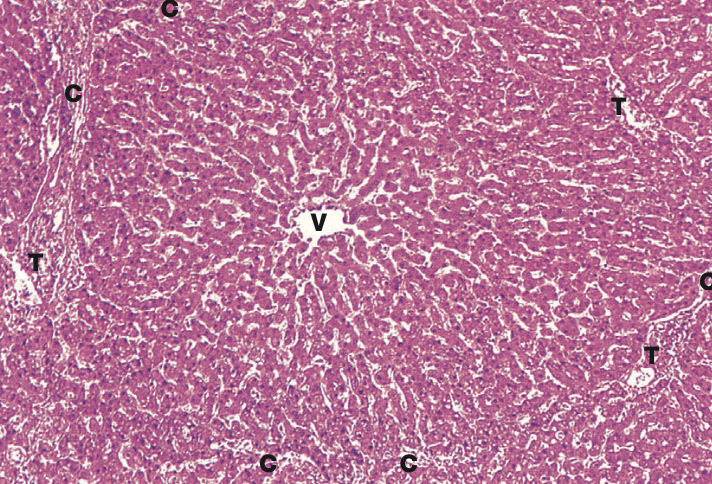

Identify the Organ and Structures?

Liver; Lobule w/ Central vein, surr by Hepato and Sinu, Portal triads in corners

Liver; Central vein, surr by Hepato and Sinu